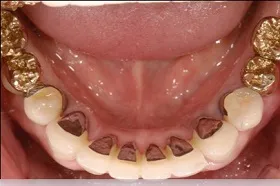

インプラント治療及び補綴治療のケース

■治療前:奥歯が無いため噛み合わせが深く下の歯が全く見えない

噛み合わせが低いため全体的に歯が削れている

■治療後:下顎 左下5・6番、右下4・6番にインプラント治療

その他の歯に補綴治療をしたことにより、奥歯もしっかりと咬むことができ、奥歯ができたことにより噛み合わせも上がって下の歯も見えるようになり、審美的にも改善された

| 主訴 | 歯科治療をしても歯がすぐに欠けてしまう 奥歯が無いため、奥歯で咬めない |

| 治療方法 | インプラント治療 + 補綴治療 |

| 治療期間 | 約1年 |

| 通院回数等 | 約20回 |

| 費用 | 約250万円(税込) |

| リスク・副作用 | 術後の腫れ・痛み |